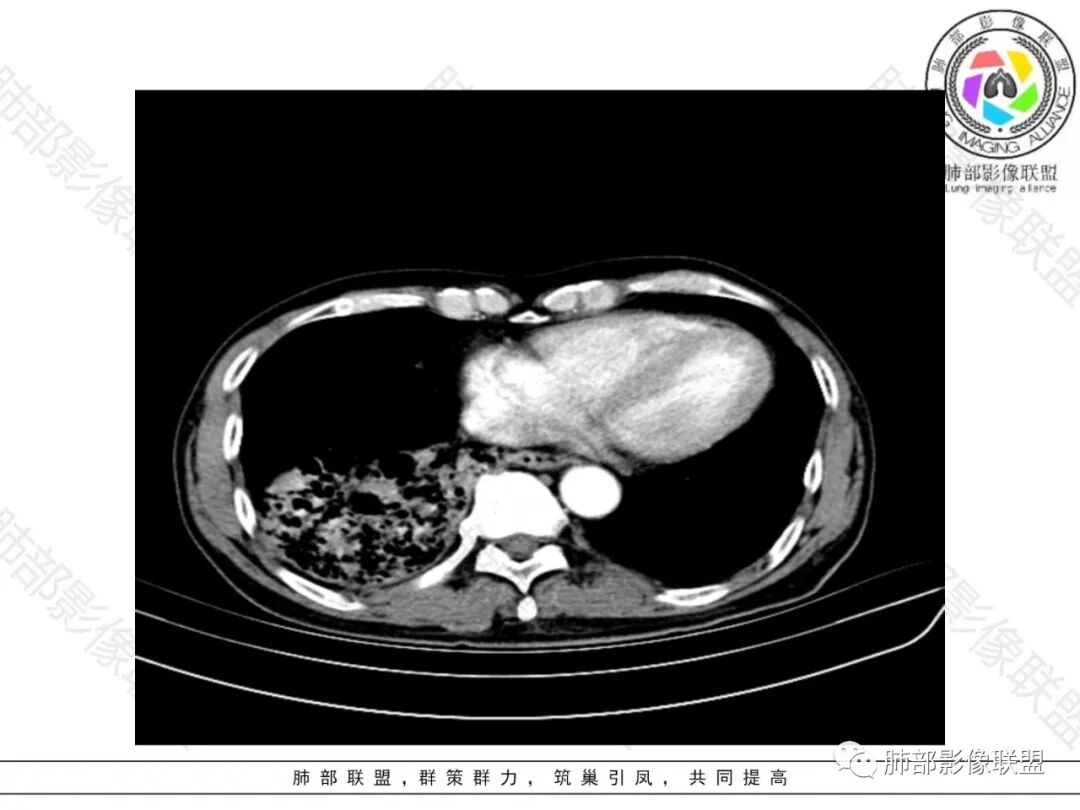

右肺下叶大团块影,斜裂膨隆,内支气管破坏,纵隔窗实质性成份少有强化(假大空),肿瘤CA125、199高,考虑粘液腺Ca右肺门淋巴结及纵隔淋巴结大,右肺下动干起始处充盈缺损(示栓塞或Ca栓;余肺叶弥散网格状改变,间质增厚及纤维化表现!

老年男性,反复咳嗽咳痰喘憋8年,加重10天,发热半天。白细胞计数明显升高(存在细菌感染可能),CEA、CA19—9升高(肺癌或间质性肺疾病引起可能)。痰培养见肺克。CT;双肺弥漫小叶间质、中轴间质增厚,胸膜下肺气肿,右肺门及右下叶可见实变影,边界模糊,内支气管走形僵硬,部分见蜂窝样改变,增强后实变区可见低密度区(粘液?),叶间裂膨隆,纵隔及右肺门见肿大淋巴结,右肺门淋巴结内见坏死。存在感染,但单纯感染难以解释支气管走行僵硬、实变内的低密度病灶,考虑恶性伴感染,肺炎性肺癌或黏液腺癌。

整个背景是一个肺气肿并间质纤维化,肺气肿以上肺为主(有些地方分不清到底是小叶中心或间隔下肺气肿伴间隔增厚还是蜂窝),左肺下叶正常结构消失,以弥漫网格为主,应该没有多少正常肺功能组织。右肺下叶肺动脉栓塞,再往下几层应该是肿大淋巴结并坏死。右肺下叶的病变考虑粘液性腺癌, 需与感染鉴别(有没有可能是肺梗死呢?)

2.影像表现:肺气肿背景,右肺下叶呈现明显网格影及蜂窝影、枯枝征,边缘膨隆、叶间裂向前方推移。病灶密度不均,前份见不规则片状实性密度区,实性部分轻度强化,边界不清,周边特征掩盖不清。支气管主要分支显示,呈枯枝征。纵隔窗病灶密度偏低,病灶内血管影边缘稍显模糊,未见明显液化坏死区。

右侧肺门淋巴结肿大,中央低密度;纵隔见轻度增大淋巴结。

3.综合分析:临床方面:慢性病程、急性发作,呼吸道症状伴发热,炎性指标升高,提示存在感染可能;CA199升高,但相对特异性不高。影像双肺气肿,右肺下叶蜂窝状改变明显,夹杂实变密度区,支气管相关但未见阻塞,较常见于感染性病变,如G-杆菌感染等。蜂窝影什么时候出现我们不得而知,实变区周边特征掩盖不清。

前后三月余病灶变化不明显,右肺门异常肿大淋巴结让人警惕恶性病变可能性。